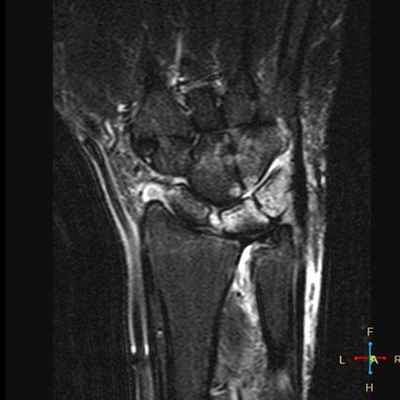

4. МРТ при остеонекрозе лучезапястного сустава:

• Т1 ВИ: ↓ интенсивности сигнала, в зоне перелома может визуализироваться линия низкого сигнала

• Последовательности, чувствительные к жидкости: изменения сигнала достаточно вариабельны; характерно раннее ↑ сигнала, позднее ↓ сигнала:

о Линия перелома темная или яркая, визуализируется не всегда

• Т1 ВИ С+: недостаток усиления предполагает наличие нежизнеспособных фрагментов:

о Не всегда является специфичной; позже может произойти реваскуляризация

о Полулунная кость: ранний коллапс вдоль проксимальной границы с лучевой костью; при отрицательном локтелучевом индексе развивается маляция полулунной кости, треугольный фиброхрящевой комплекс может быть утолщен или порван